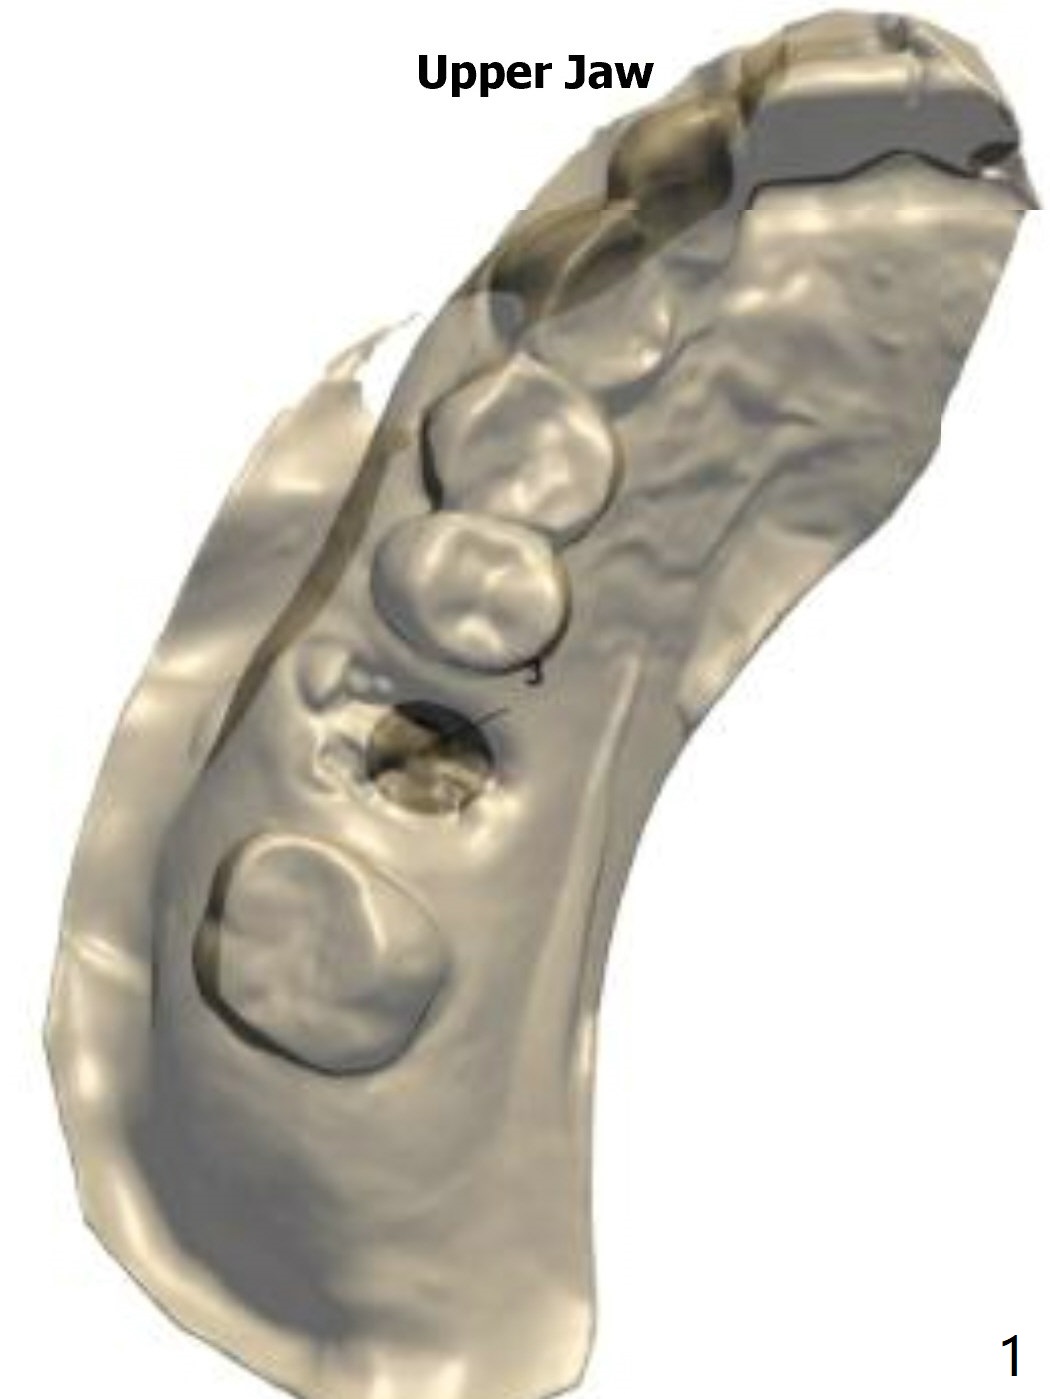

Upper

Molar Immediate Implant,